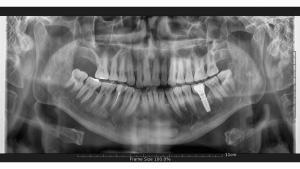

Bunun sebebi, bazı durumlarda çıkarılması gereken dişlerde enfeksiyon olabileceği, hatta bunun hafif bile olsa mevcut olabileceğidir. Enfeksiyon için ilaç kullanarak, hastalarımızın implant operasyonu ve sonrasındaki süreci daha konforlu geçirmelerini sağlıyoruz. Marmaris, Türkiye’deki kliniğimize tam bir diş implantı için gelen hastalarımıza, öncelikle detaylı bir muayene yaparız, bunun için panoramik röntgen ve ağız muayenesi gerçekleştiririz. Muayene sonuçlarına dayanarak, doktorlarımız bir tedavi planı oluştururlar. Ardından, hastalarımıza en iyi tedaviyi sağlamak için implant cerrahisi sürecine geçeriz.